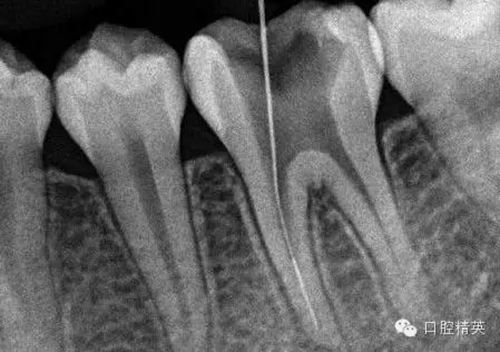

9,斷針取出術(shù)后X-P,RCT待續(xù)。。。